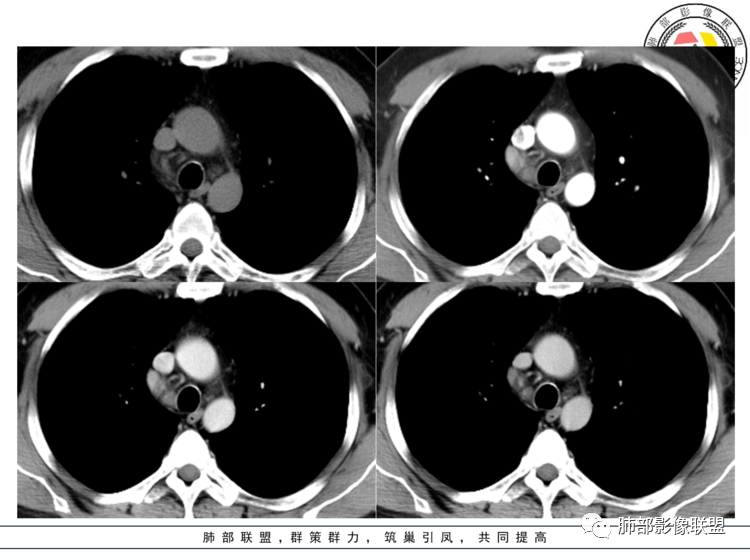

男性,40岁,前纵隔类圆形肿块影,边界清晰,密度均匀,边缘可见浅分叶,增强扫描病灶强化较,强化低于血管,与周围血管分界清晰,常规考虑CD(中间型),鉴别神经内分泌肿瘤,后者强化不明显。

病灶位于上腔静脉内侧,定位没有疑问,来自纵隔。上腔静脉内侧有什么,有淋巴。膈神经在外侧。迷走神经在后侧

副节瘤,和cd都是明显强化,前者比较容易坏死,cd比较均匀,更符合后者的表现

中年男性右上纵隔椭圆形软组织肿块,边界清,密度均匀,明显均匀强化(峰值在动脉期),周围见小血管影进入及有小淋巴结,考虑CD>副节。

纵膈内上腔静脉内后方肿块,边缘清晰,形态不规则,周围可见多发小淋巴结,明显强化。纵膈内强化明显的常见有CD,异位甲状腺,副节瘤,血管瘤。异位甲状腺平扫密度高一些,钙化常见,不符。副节瘤好发生于后纵膈、主动脉旁、肺动脉旁、心包内,而且容易坏死,一般沿神经节分布,纵径大于横径。综合考虑:CD>副节瘤。

40岁,男性。右中上纵隔见实性团状软组织影,密度均匀,边界光整清晰,与周围结构分界清晰,增强后动脉期明显均匀强化,静脉期延迟期强化逐渐减低。定性:良性病变或肿瘤,常规考虑巨淋巴结增生CD,需鉴别诊断的疾病有1神经源性肿瘤如神经鞘瘤,沿纵轴生长,横轴大于纵轴,但一般有AB区,有囊变坏死,多见后纵隔,强化渐进性强化,发生前中纵隔的恶性程度高,此例不太支持,但不排除;副神经节瘤,囊变多见,不支持;节细胞瘤,一般纵轴大于横轴,不支持;2神经纤维瘤SFT,蛇蚊征,待排,3孤立性转移瘤,少见,一般有原发肿瘤病史,肿瘤标志物异常,环形强化,不支持。4淋巴瘤,常多发淋巴结肿大,少见囊变坏死,待排。5异位甲状腺,一般平扫密度较高,此例不支持。

患者中年男性,体检发现纵隔占位。胸部CT:右上前纵隔不规则占位灶,位于上腔静脉后方,血管无推移,边缘光滑,密度均匀,增强动脉期明显强化,综合考虑良性病变,巨大淋巴结增生症可能大。鉴别神经源性肿瘤。

中年男性,上纵隔气管旁软组织肿块,边界清楚,与周围结构脂肪间隙存在,长轴与气管一致,增强明显不均匀强化,静脉期及延迟期强化稍减退。强化明显的纵隔肿瘤,考虑CD,鉴别副神经节瘤。淋巴瘤强化不符合,神经鞘瘤没看到明显的A区、B区,暂不考虑。

右前中纵隔软组织肿块,有钻缝生长特点,边界清,周围脂肪血管未见受侵,增强动脉期明显强化,明显持续强化,内部及周围见血管,周围见小淋巴结,考虑CD,鉴别淋巴瘤,强化不支持;胸腺瘤,不常见部位,形态也不支持;副节瘤,这么大肿块坏死囊变应很明显;神经内分泌肿瘤,强化太均匀、生化不支持,周围结构改变也不符合;神经鞘多有AB区,渐进性强化!

中纵隔内类椭圆形软组织占位,密度均匀,边界清晰,与周围结构分界清晰,腔静脉向外推移,周围见数个增大淋巴结,增强扫描明显均匀性强化,考虑良性,CD可能性大,鉴别神经源性肿瘤。

CD!鉴别淋巴瘤,结节病,淋巴结结核。①淋巴瘤:纵隔淋巴瘤的分布以前纵隔和支气管旁组最常见,其次是气管与支气管组和隆突下组,增强扫描呈轻度强化。②结节病:常纵隔及肺部病变同时存在,纵隔及两侧肺门淋巴结肿大、肺间质性改变为主,以患者症状轻、症状进展缓慢为特点。③淋巴结结核,淋巴结肿大多为一侧性,增强扫描呈环形强化。肺内多有结核病变,加上临床可鉴别。巨淋透明血管型

定位,中纵隔,上腔静脉向前推移。椭圆形软组织影,边界清晰,密度均匀,周围脂肪间隙清晰。增强明显均匀强化。

考虑,良性,CD,鉴别副节瘤。